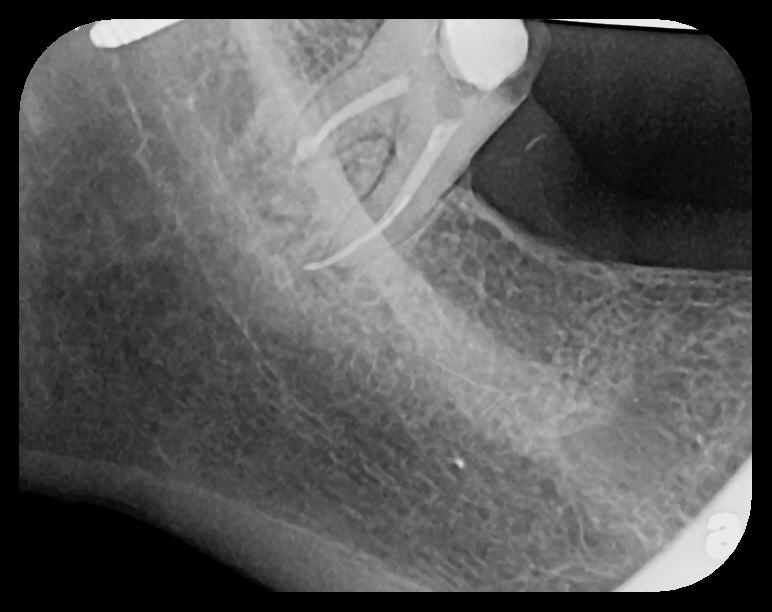

Fig 10.

A hemostat was used to obtain this PSP PA image of a potential fixed

prosthesis abutment, tooth No. 32. The hemostat is visible in the upper

left corner of the image. Hemostat stabilization of an HW sensor is

not possible and can damage the sensor if attempted.

Figure 10